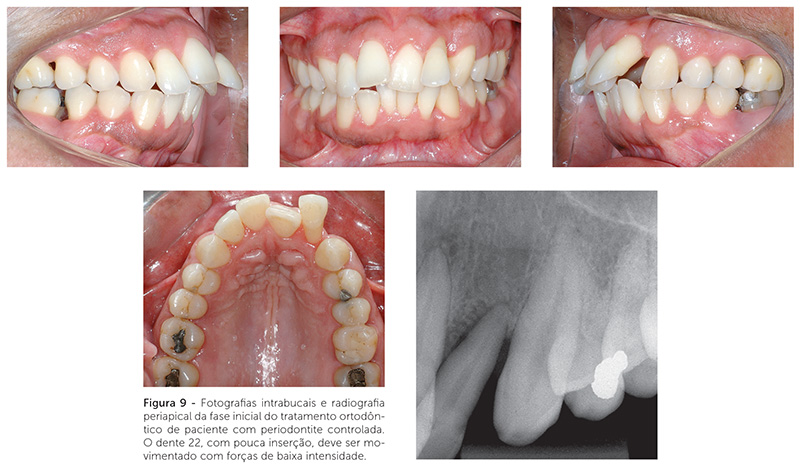

O tratamento ortodôntico de um paciente com doença periodontal não pode ser visto como um tratamento comum. Todos os casos ortodônticos exigem diagnóstico e planejamento efetivos, mas, em um paciente periodontal, esse exercício torna-se mais difícil. Deve-se ter em mente que todo tratamento deve beneficiar o paciente. Quando o periodonto está comprometido e há um planejamento ortodôntico falho, a chance do paciente ser prejudicado por um tratamento mal conduzido é grande. Por isso, esses casos exigem integração, de modo que o paciente não deve iniciar a movimentação ortodôntica sem a aprovação do periodontista, e esse deve acompanhar a situação periodontal durante todo o tratamento ortodôntico25,26. Um exemplo de movimentação dentária em paciente com pouca inserção periodontal pode ser visto nas Figuras 9, 10 e 11.

Não se deve fazer movimentação dentária na presença de doença periodontal, por diversas razões: 1) pode causar um abscesso periodontal, principalmente na presença de bolsas profundas; 2) após a terapia periodontal, ocorre a eliminação do edema e a consolidação do colágeno gengival, ocorrendo, então, acomodações dentárias que podem ser favoráveis ao posicionamento dentário e reduzir a duração do tratamento ortodôntico subsequente; 3) ao se iniciar um tratamento ortodôntico, é importante saber a altura e a espessura óssea ao redor dos dentes, e isso o periodontista, durante o tratamento cirúrgico, é capaz de observar e informar ao ortodontista25,26.

O tratamento ortodôntico de pacientes com doença periodontal controlada é, muitas vezes, um tratamento mais curto e direcionado. A redução do periodonto de suporte gera importantes implicações para o movimento dentário ortodôntico. Existe uma relação linear direta entre o suporte alveolar e a localização do centro de resistência. Conforme o osso alveolar de suporte vai sendo reduzido, o centro de resistência vai se movendo apicalmente. A intensidade e o ponto de aplicação de força durante o tratamento ortodôntico devem ser adaptados em tais situações. As forças utilizadas devem ser de magnitudes menores que aquelas utilizadas em periodontos saudáveis. Para que o movimento dentário seja mais controlado — haja vista que o centro de resistência encontra-se localizado mais apicalmente —, a colagem dos acessórios pode ser realizada mais gengivalmente.